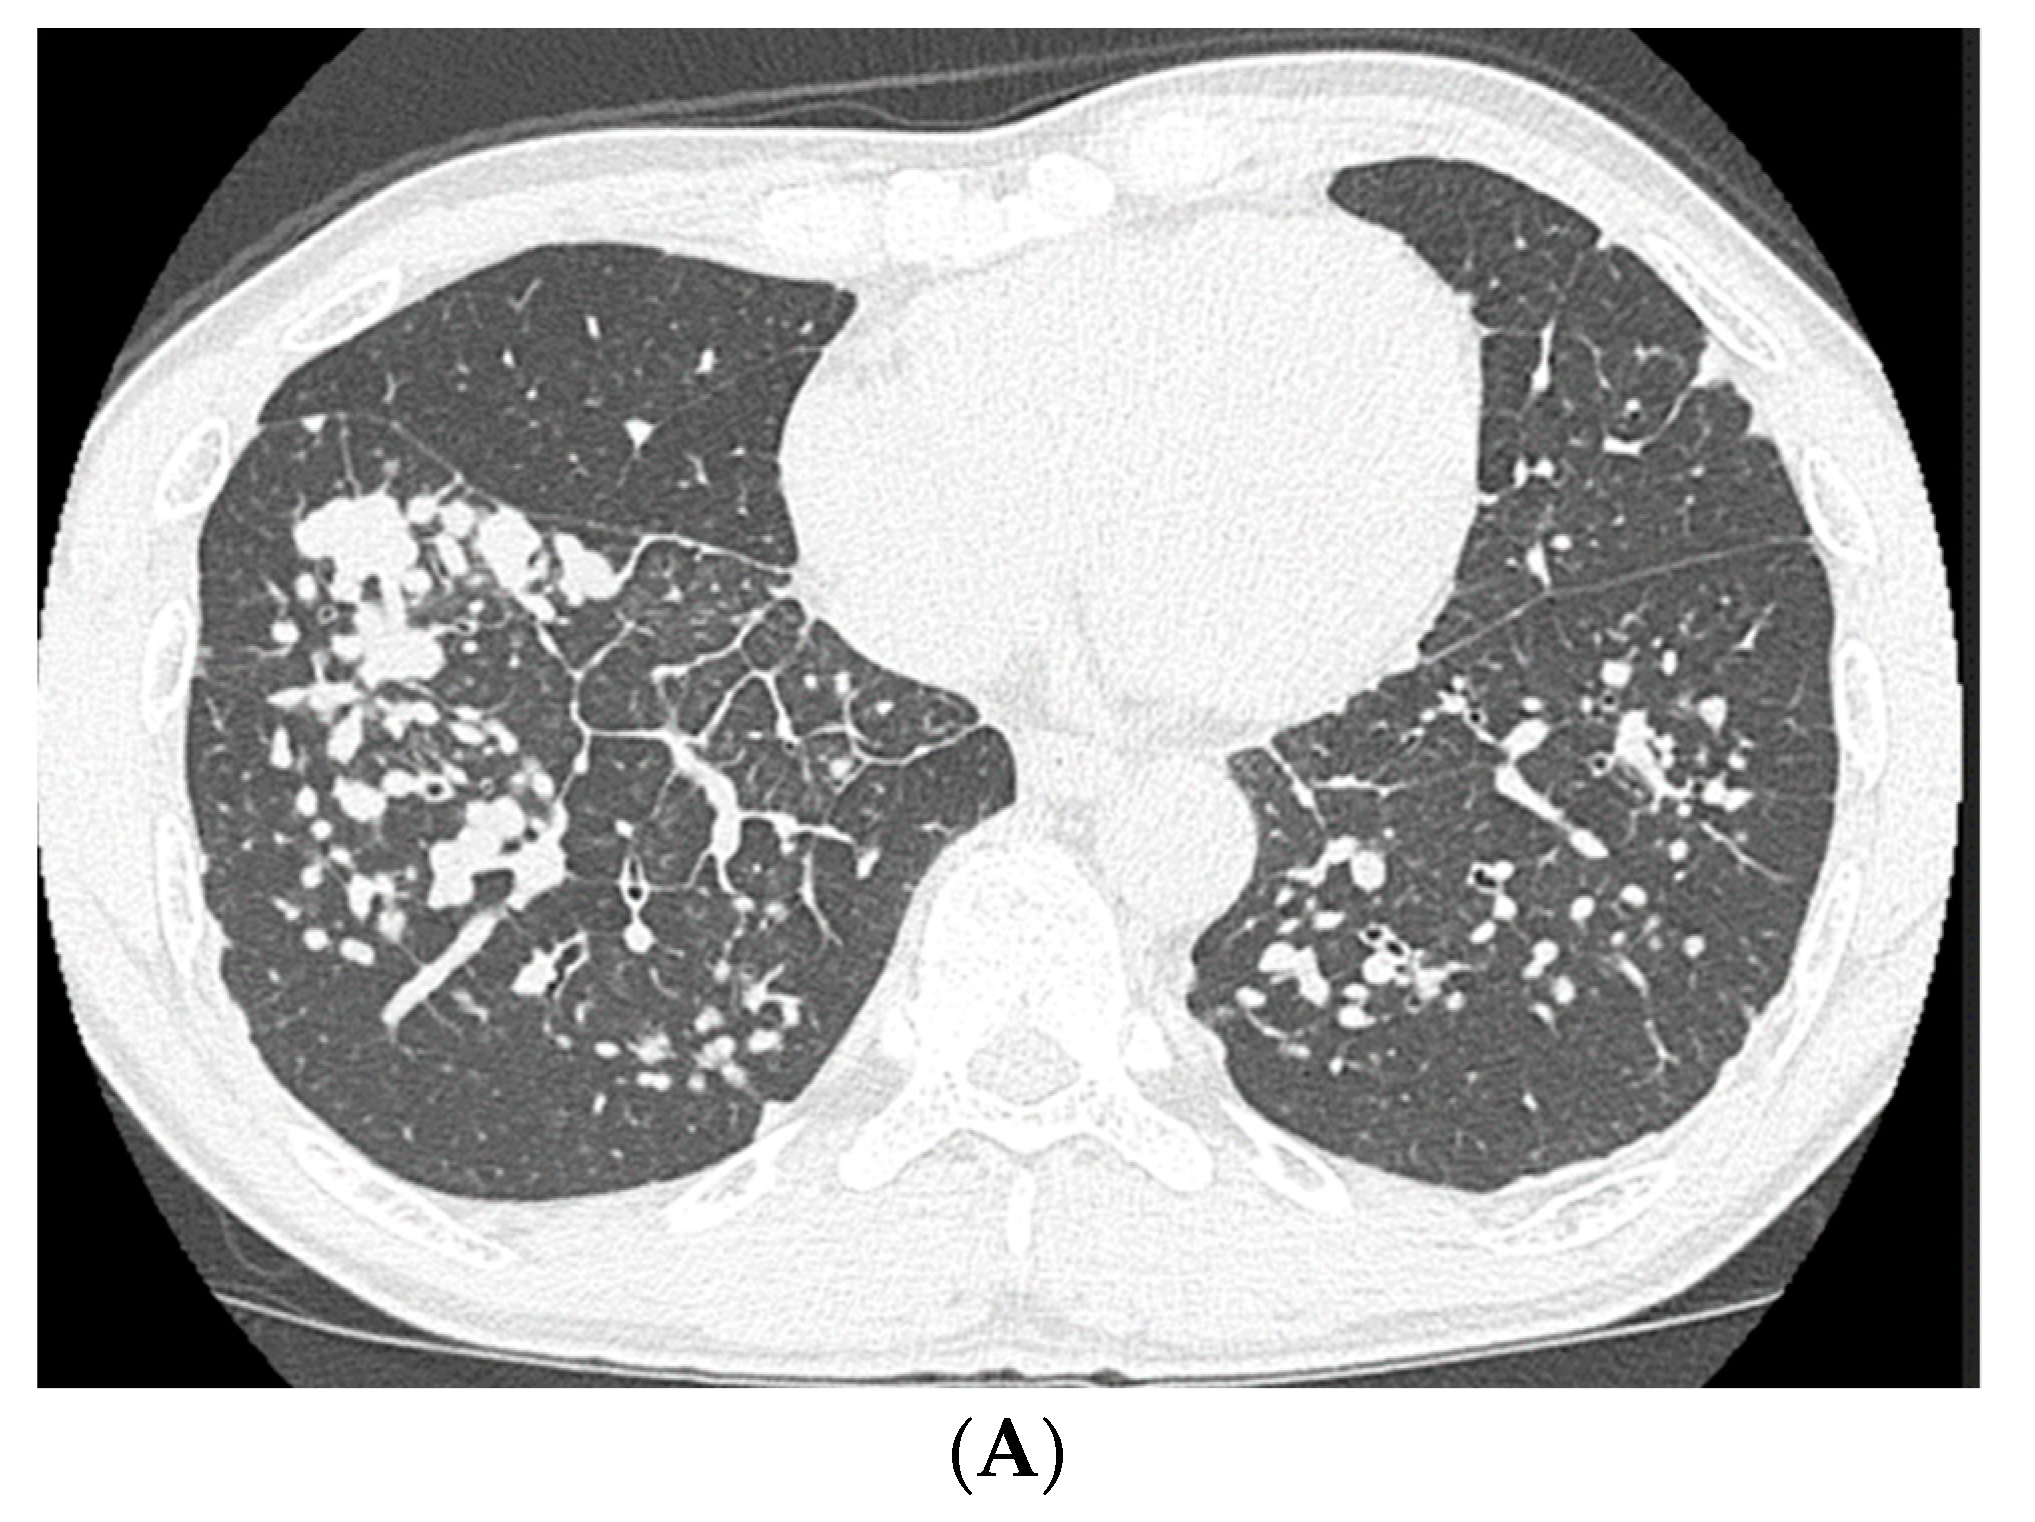

Based on his history of occupational exposure and his clinical, radiological, and pathological findings, the patient was diagnosed with pneumoconiosis with a sarcoid-like reaction. He did not receive any medical treatment, such as corticosteroid administration; however, he stopped smoking and changed his occupation to avoid further exposure to dust. Two years later, the HRCT showed an increase in the nodular shadows (Figure 5A). However, the shadows were observed to have decreased after 5 years (Figure 5B).

Figure 5.

(A) High-resolution computed tomography of the chest after 2 years, showing an increase in the nodular shadows. (B) High-resolution computed tomography (HRCT) of the chest after 5 years, showing a decrease in nodular shadows.